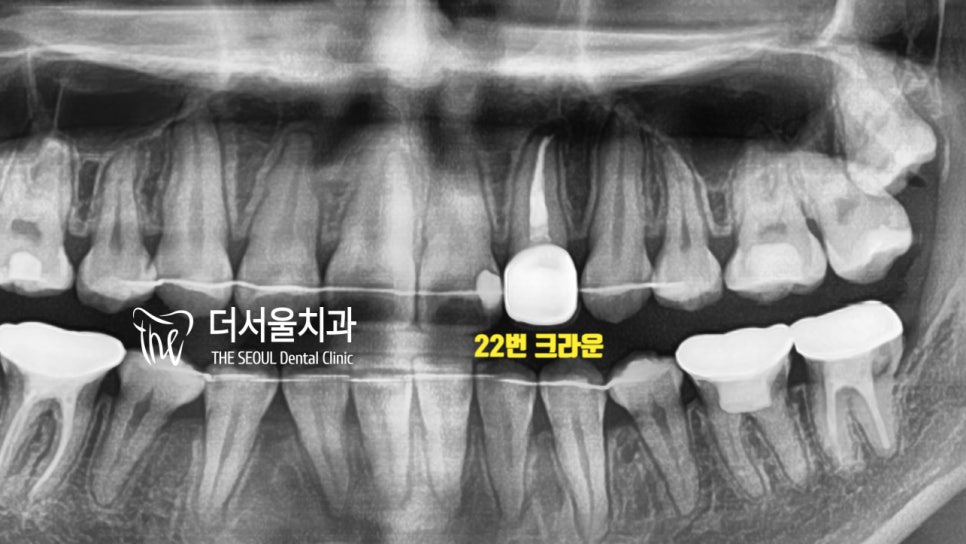

와~ 한눈에 봐도

제위치를 벗어난 것들이 많았는데요.

아 참! 전에 측절치 22번에

우식 (충치, caries)과 금(crack)이

나타났던 거 기억나실까요?

인비절라인 발치 교정이 마무리되었으니

이곳부터 치료를 도와드려야겠네요.

눈에 잘 띄는 앞니라

더서울에서는 위화감 없이

잘 어울릴 수 있도록

색조, 형태 재현에 심혈을 기울였습니다^__^

이전에 크라운을 올려드렸던

22번도 잘 어우러지고 있네요.